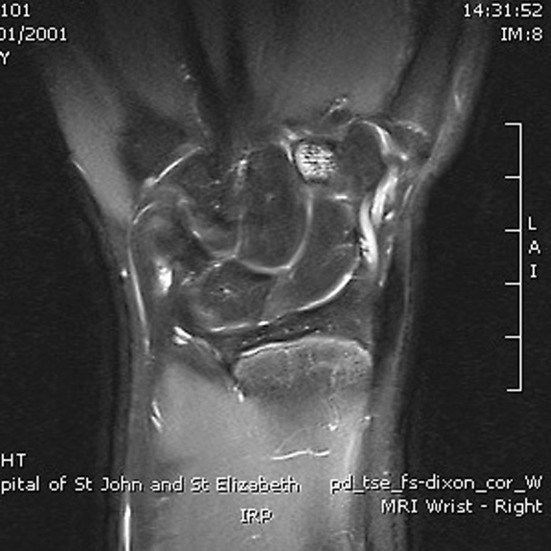

The incidence of paediatric occult fracture was 36.5 % (n = 23). Patients with an occult fracture had an average of 1.5 MRI findings. 26.1 % of patients with fractures had an associated bone contusion, 8.7 % had concomitant injuries to the TFCC (1 sprain, 1 tear), and one patient had an injury to the extrinsic ligaments. Further breakdown and comparison is provided in Table 2. In the paediatric population, the distal radius (Fig. 2) was twice as commonly fractured as the scaphoid (Fig. 3a, b), whilst the scaphoid, lunate, and trapezoid (Fig. 4) were the only carpal bones affected. In comparison, Bergh et al. [13] and Pierre-Jerome et al. [12] report an adult occult fracture incidence of 28 and 23.2 %, respectively, with the former study identifying occult fractures of all carpal bones excluding the pisiform and hamate. These results suggest that occult paediatric wrist fractures are twice as likely to occur in the distal radius as they are in the scaphoid, whereas the incidence of occult fracture is equally spread in both bones in the adult population. Furthermore, the number of carpal bones sustaining occult fractures is limited in children in comparison with adults.

Coronal PD fat sat: intense marrow oedema within the distal radius metaphysis. Small linear area consistent with trabecular fracture